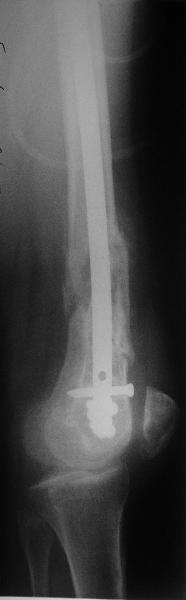

Отправитель: Alexander Chelnokov 20 Февраль 2009, 18:28

Это результат через полгода. К сожалению, пациент больше не приезжал на контрольный осмотр.

Чтобы больной не смог сгибать колено, выстоять в сустав железо должно побольше значительно, чем на 1 мм. В приложении снимок с выстоянием ммм на 3, видна и функция колена. Хотя клиника импинджмента была, но даже не на один восклицательный знак. После удаления стержня проблемы и вовсе рассосались.

Я только что показал наш давний пример аналогичного остеосинтеза. Движения были начаты сразу, использовали функциональную шину.